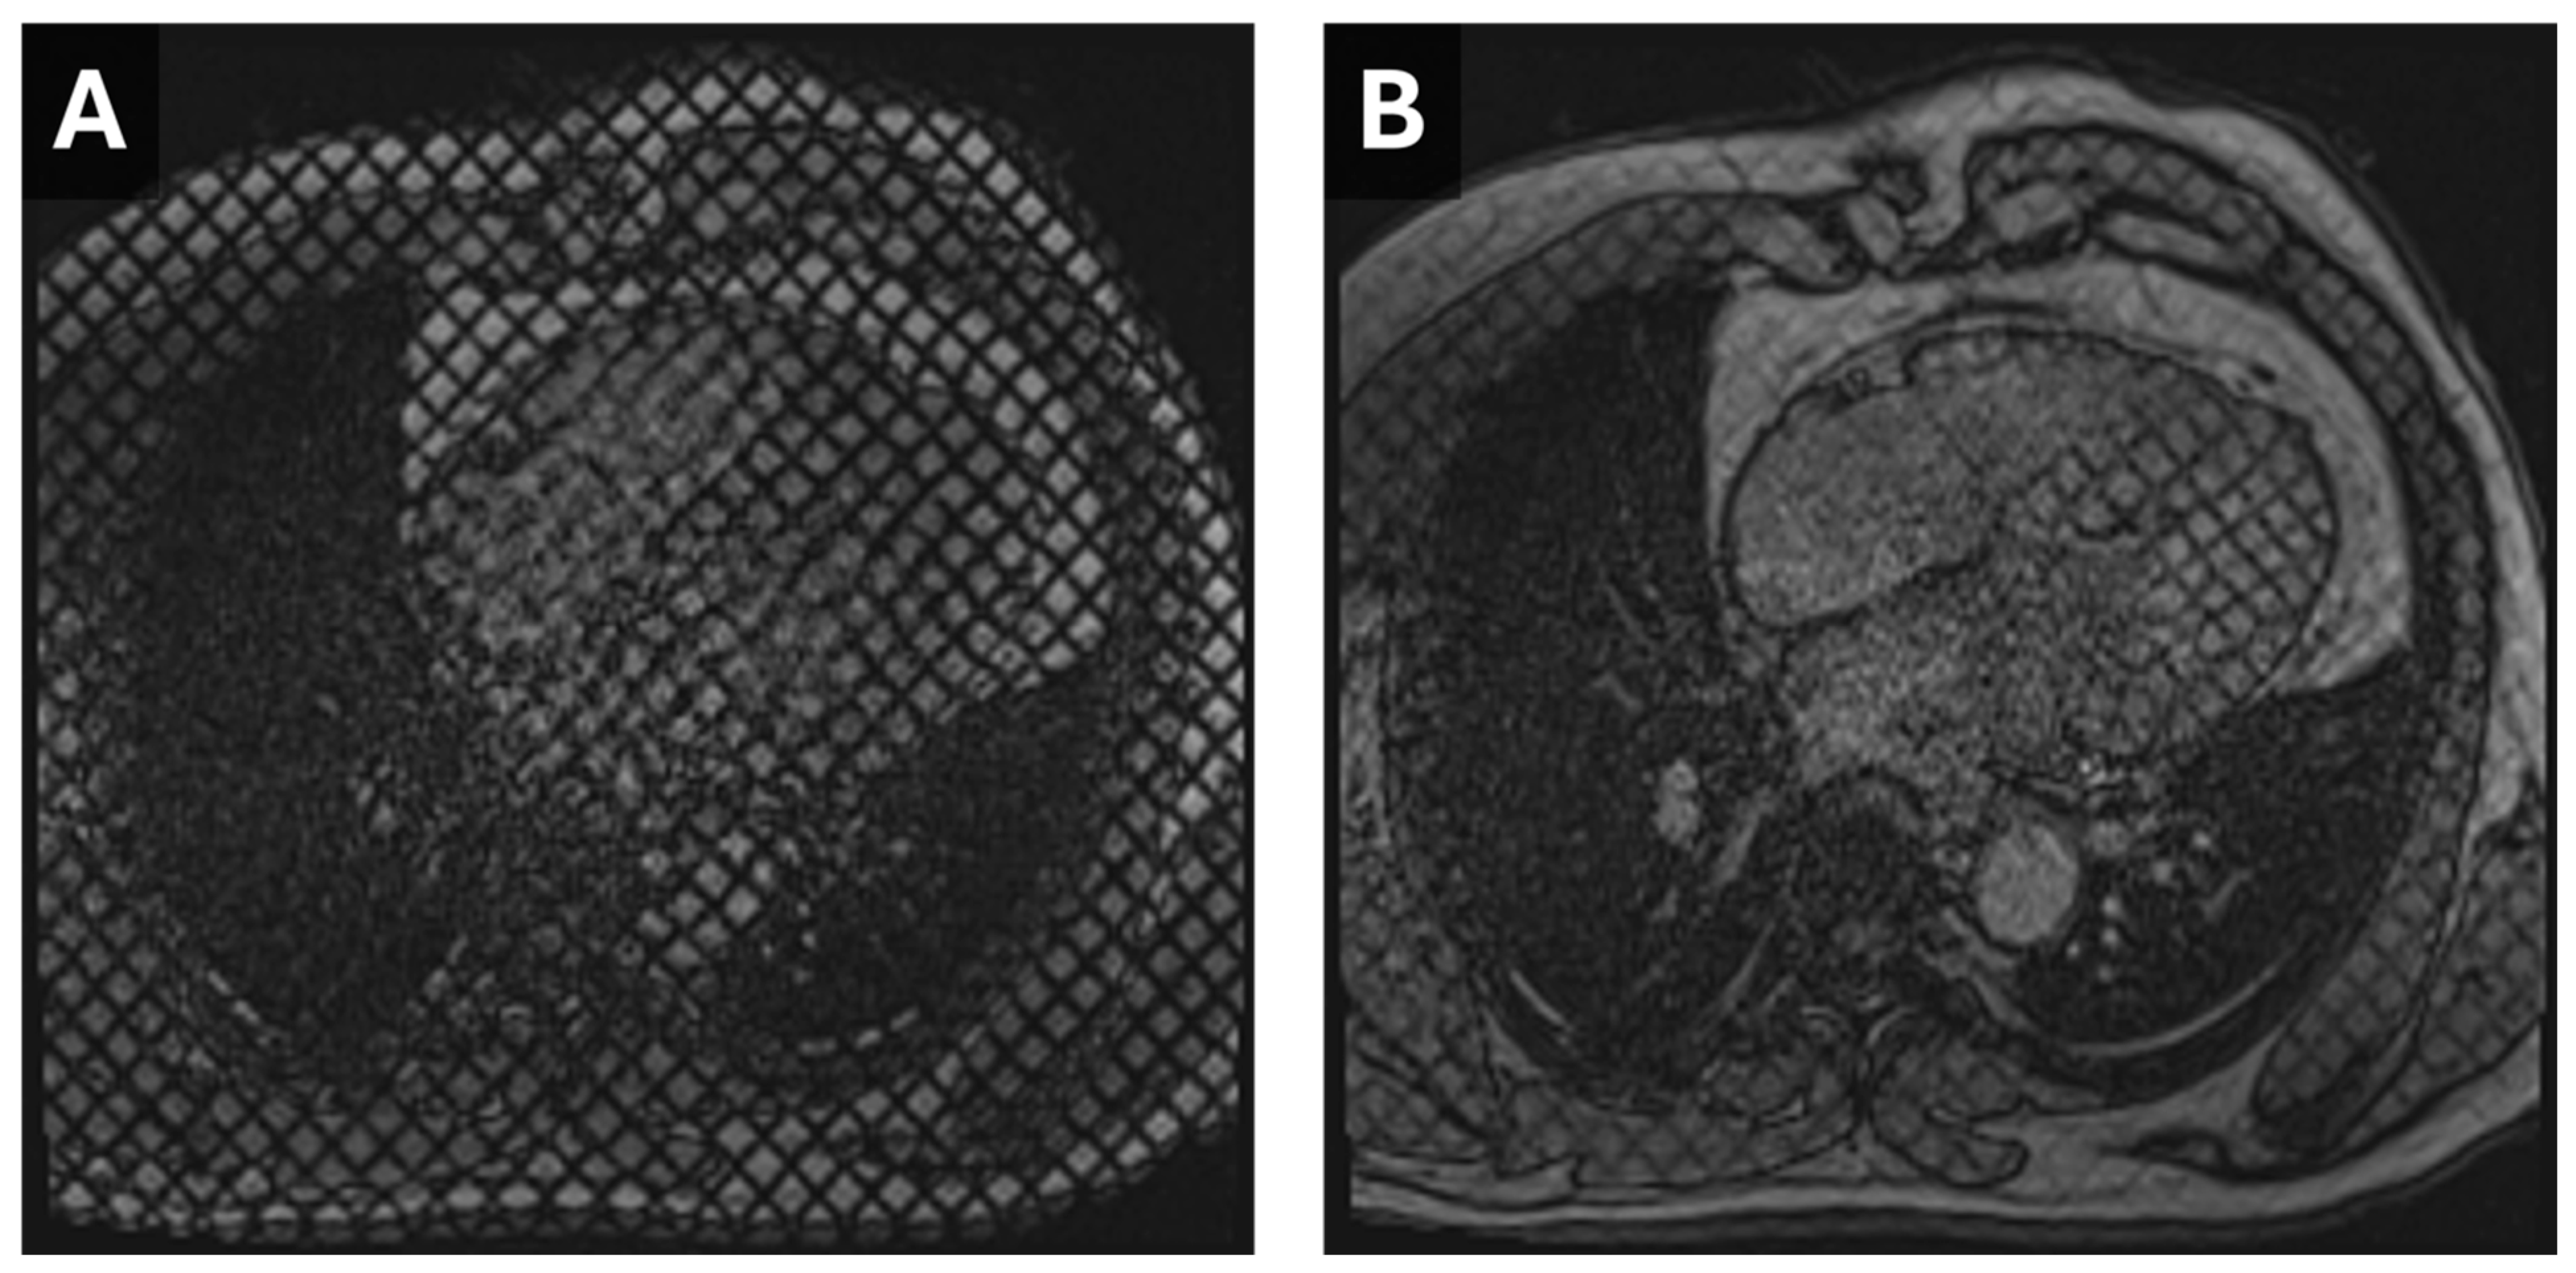

Figure 3.

Cardiac MR Strain Evaluation. Static horizontal long-axis diastolic (A) and systolic (B) grid-tagged images from a cardiac MRI. Deformation of the grid as the myocardium contracts can be used to estimate strain.

Figure 4.

Cardiac MR Strain Evaluation. Cine horizontal long-axis grid-tagged images from a cardiac MRI. Deformation of the grid as the myocardium contracts can be used to estimate strain.